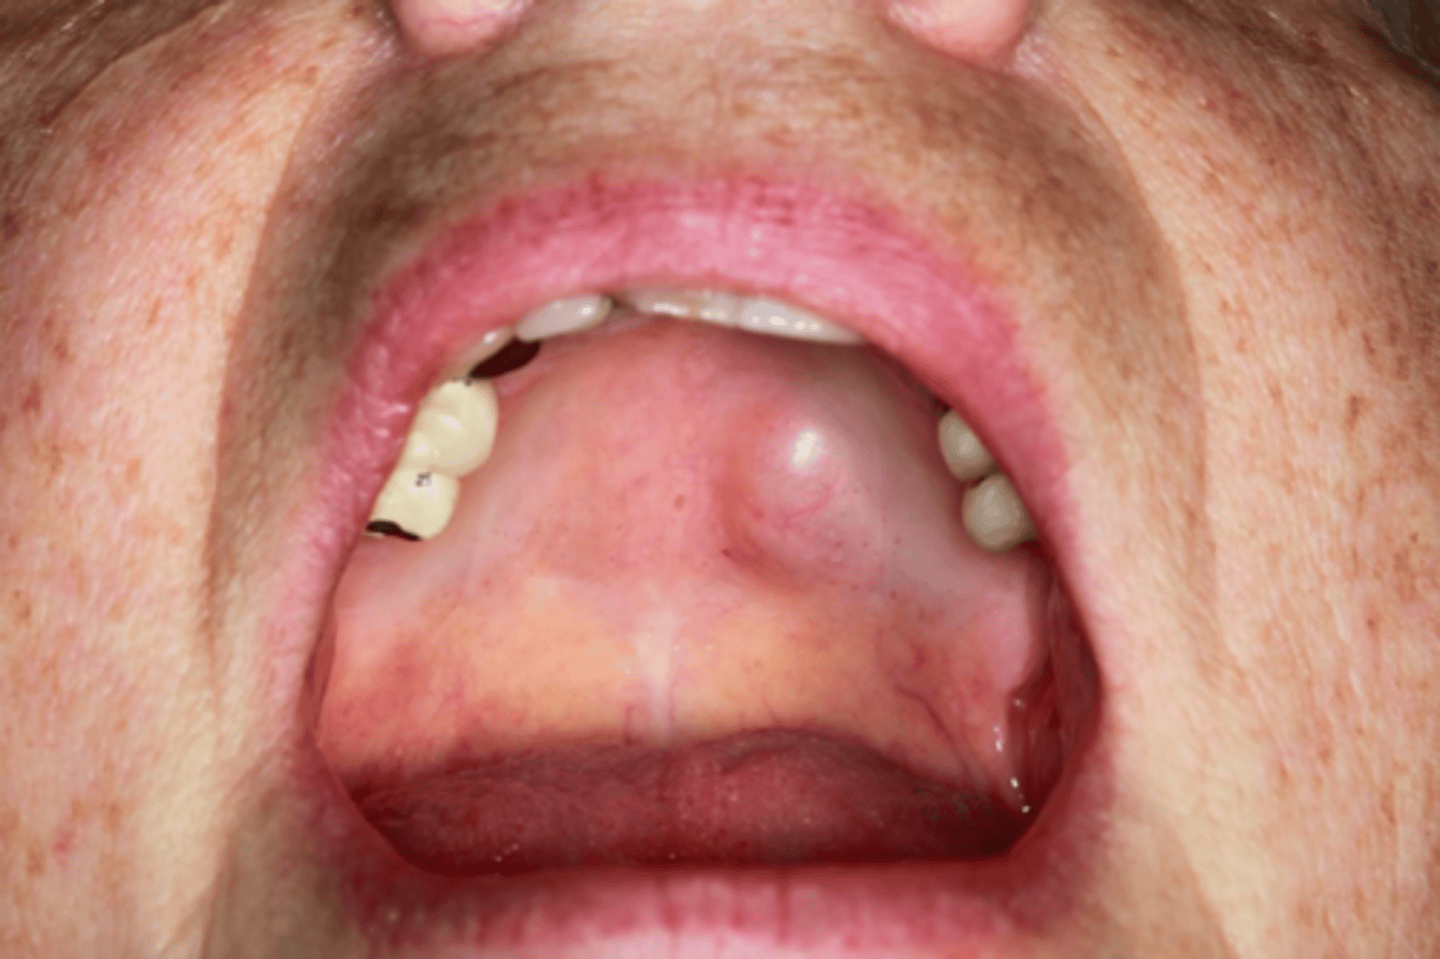

Lipoma

patient presents with nodule on the floor of the mouth that is and slight yellowish tint. Histopathology showed Well-circumscribed mature adipose tissue. What do you suspect?

Lipoma

ID the pathology:

conservative excision